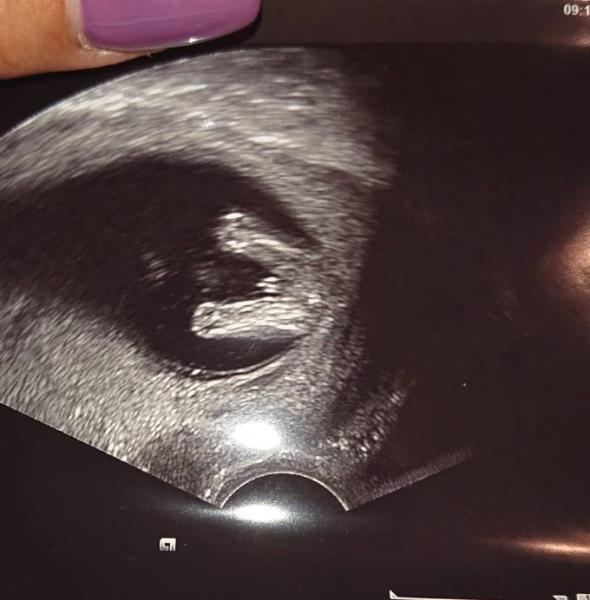

Naja der Arzt beginnt mit dem Ultraschall und Mädels... Das allererste was man sieht war ..... (Siehe Bild)

Dass mein Baby sich sooo früh zeigt ist unglaublich .. bin sooo glücklich .. viele warten soo lange und mein kleines Baby sagt "hallo Mama Guck Mal ich bin ein kleiner Junge"

Findet ihr dass ist schon ein klares Bild? Manchmal sagt man ja vielleicht könnte es doch anders sein ? Es ist halt echt noch sehr früh .. Und noch eine Frage hätte ich.. Und zwar geht es um die Feier die meine Freundin organisiert ... Sollte ich ihr sagen, dass ich das weiß? Oder sollte ich so tun als wusste ich es nicht ? Sie hat schon sooooo viel für diese Feier gemacht :-(

Ich denke, da kann man noch nix sicher sagen. So einen nub haben beide Geschlechter in dem Alter. Theoretisch sagt es etwas aus, wo der hinzeigt aber das sieht man aus der Perspektive eigentlich nicht. Ich würde mich auf Junge nicht so versteifen. Oder hat der Arzt das gesagt?

Das hier könnte genauso gut ein Mädchen sein